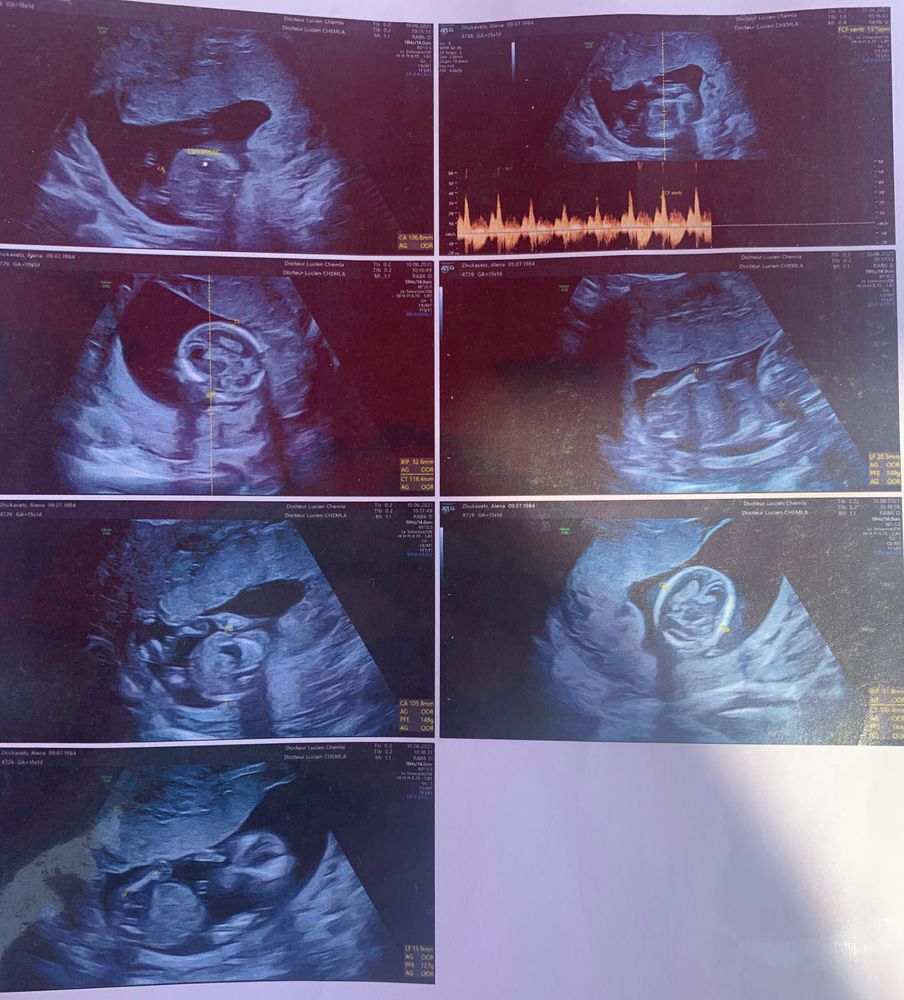

Узи 15 недель кто может помочь ?)

Девочки , сегодня была на узи 15 недель врач сказал рано ещё ) мне кажется что мальчик но я ничего не понимаю в узи ,вообще не знаю куда смотреть ))там на узи видела пуповину хорошо , а тут фото только такие .может есть предположения

Ничего не понятно,не знаю что Вы там рассмотрели,половина фото это фото головы?

Здравствуйте! Качество УЗИ отвратное, не понятно вообще с таким темпом вообще не понятно, пожалуй придется подождать до 20 недель, сдесь даже черты лица не видно не говоря не о чем, я куда хожу там можно все рассмотреть вплоть до гласэз, волос и мимики .. Я думаю что возможно мальчик, но не факт . Лёгкой беременности, пол не настолько важен как хорошее развитие малыша.